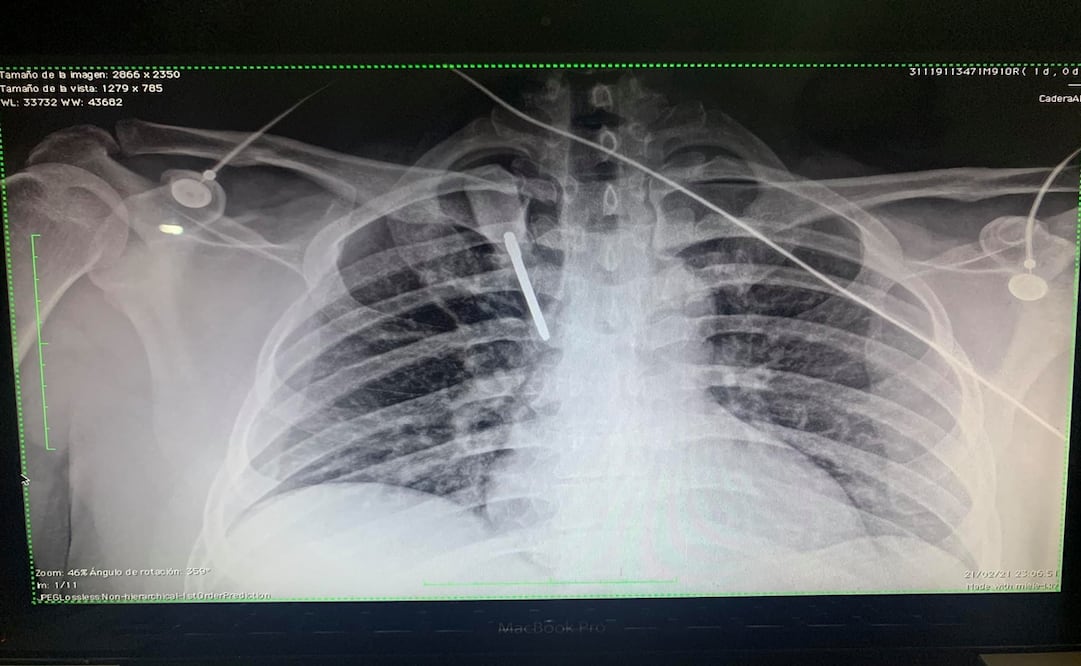

Al lugar llegó un militar y un vigilante y le dijeron que no se moviera porque tenía clavado un desarmador en el pecho . "Todavía no puedo entender porque las personas que nos dedicamos a salvar vidas somos agredidos de esta manera, siento coraje, impotencia, decepción y tristeza de vivir en un país donde a gran parte de la sociedad no le importamos", escribió el joven.

Juan Carlos Soria Maturino, aseguró estar vivo por un "milagro, porque hay un ángel cuidándome y por los médicos, enfermeras, camilleros, técnicos radiólogos y demás personal que se encargaron de ayudarme de inmediato".